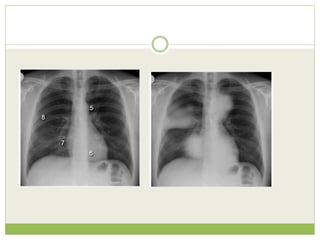

Simulated silhouette signs

1 - Left heart border - Lingula disease

2 - Hemidiaphragm - Lower lobe lung disease

3 - Paratracheal stripe - Paratracheal disease

4 - Chest wall - Lung, pleural or rib disease

5 - Aortic knuckle - Anterior mediastinal or left

upper lobe disease

6 - Paraspinal line - Posterior thorax disease

7 - Right heart border - Middle lobe disease

8 - Density above horizontal fissure* - Anterior

segment of the right upper lobe